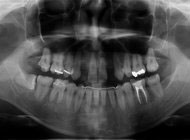

インプラントは天然の歯と同じく、細菌と咬み合わせの力によって、保存不可能となる場合があります。そのため、むし歯、歯周病の細菌がどれだけ口腔内に繁殖しているか、咬み合わせがどうなっているのか、理想的な咬み合わせの歯をつくるために、インプラントのポジションを考えた時に、その部分の骨は3次元的にどうなっているのかなどを術前に把握しておく必要があります。

全体のむし歯、歯周病の有無、顎の間接の状況、副鼻腔の炎症の有無、2次元的な顎の骨の厚みなどがわかります。